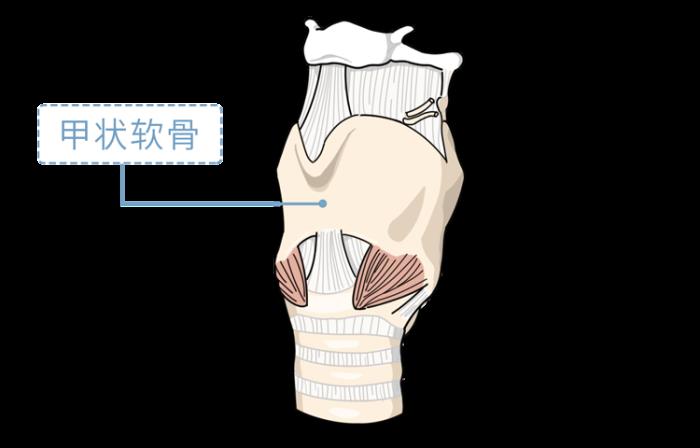

人的喉咙由11块软骨作支架组成

其中最主要、体积最大的一块

被称为甲状软骨

不论男女

当我们在母胎中2个月时

这块软骨就开始发育

并会在出生后持续长5-6年

此时它的形状较小

一般不会突出